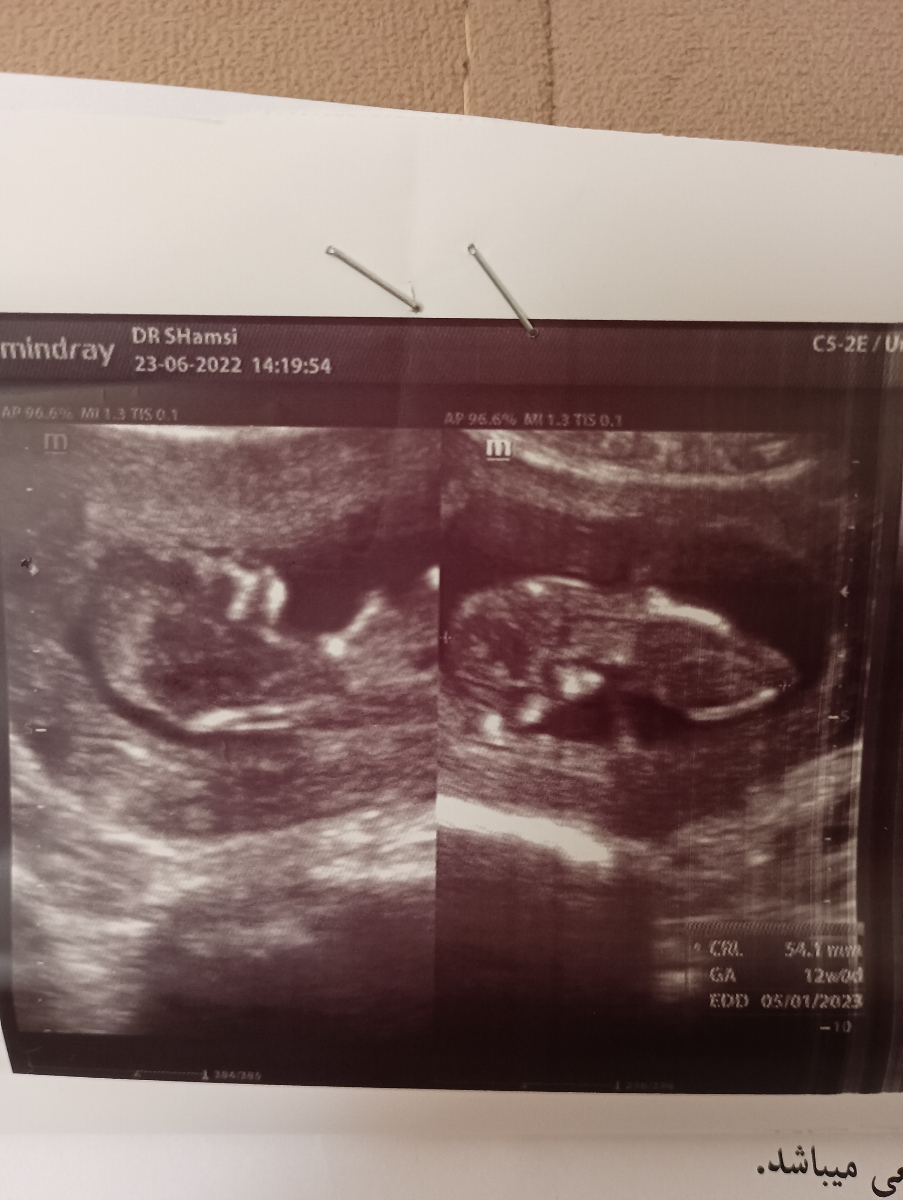

سلام وقت بخیر خانوم دکتر عزیز . من امروز رفتم سونو ان تی که خدمتتون سونو رو ارسال میکنم ولی آزمایشش رو قرار فردا برم .

پرسش (1401/06/23):

تفسیر آزمایش و سونو NT هفته ۱۲

اصولا طبق دستورالعمل ها اصلا دیده شدن با نشدن nb در سونوگرافی 12 هفته اهمیتی ندارد بنابراین خودتان را نگران نکنید. مجموعا در سونوگرافی شما تمام موارد بررسی شده از جمله وضعیتجنین، حجم مایع آمنیوتیک، ضربان قلب، جفت و همچنین میزان ان تی (NT) در محدوده نرمال قرار دارد و از این بابت جای نگرانی نیست فقط باید منتظر نتیجه آزمایش خون هم باشیم.

کیست کورپوس لوتئوم دیده شده نیز همان بقایای فولیکول است و اهمیتی نداشته و در اغلب موارد خود به خود در طی سه ماهه دوم برطرف می شود. تنها کاری که باید انجام داد این است که تحت نظر پزشک باشید تا روند کیست پایش شود. اما در مورد آزمایشات شما سطح قند خون عالی است و هیچ مشکلی در سایر موارد آزمایش ندارید. فقط هنگام دادن نمونه ادرار خودتان را تمیز کرده و از وسط جریان ادرار نمونه گرفته بودید ؟ ترشحات واژینال دارید؟ اگر دارید چه ویژگی دارند؟